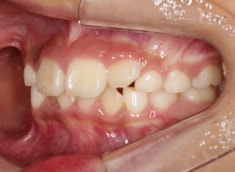

小児期ケース:叢生(ガタガタ)

治療前